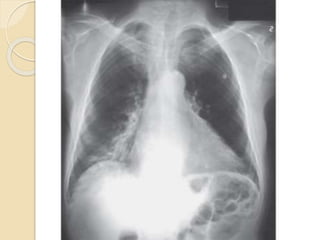

CXR

 Cardiomegaly may be present in c/c

MR or in ischemic or functional MR .

 LA body and appendage dilatation is

frequent, but giant LA is rare.

 annular calcification, seen as a C-

shaped density below the posterior

leaflet, is frequent.

 signs of pulmonary hypertension or

pulmonary edema are rarely

observed.